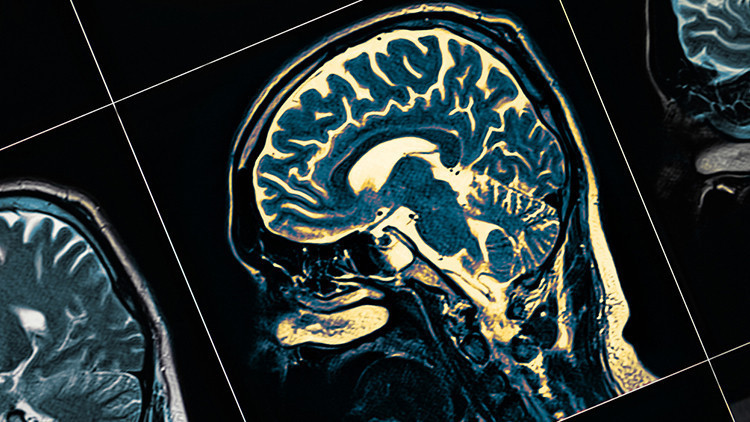

Uzmanlara göre, Alzheimer'ın ortaya çıkış nedeni, beyinde uzun yıllar boyunca biriken zararlı amiloid beta proteinleri. Bu protein birikimleri yıllar içinde katılaşarak plaklara dönüşüyor. Bu plaklar da beynin normal fonksiyonuna zarar veriyor, hafıza kaybına ve kafa karışıklığına neden oluyor.

Ancak bunun sıradan bir aşı olduğunu söylemek de mümkün değil. Son 1 yıldır gündemimizden düşmeyen Covid-19 aşılarının ya da her sene olduğumuz grip aşılarının aksine, Alzheimer aşısı, insanları enfeksiyondan korumuyor. Onun yerine beyinde bulunan ve mikroglia adı verilen bağışıklık hücrelerini harekete geçirerek amiloid oluşumlarına saldırmalarını sağlıyor. Böylece hastalığın daha ilk aşamalarındayken yani çok fazla hasar ortaya çıkmadan yavaşlatılması hatta durdurulması amaçlanıyor.